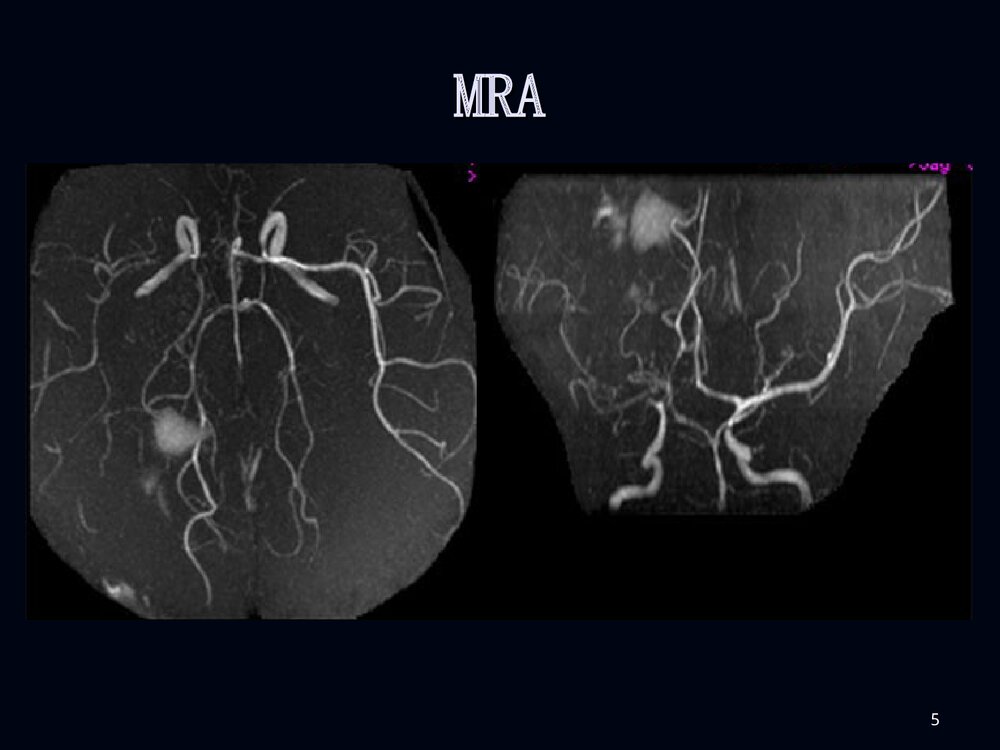

1烟雾病临床和影像诊断烟雾病临床和影像诊断2男性,男性,2020岁突发剧烈头痛岁突发剧烈头痛11小小时时3脑室穿刺脑室穿刺引流后增引流后增强强CTCT4MRIMRI5MRAMRA67病例病例22F、38Y,右侧肢体无力伴言语不清24天8MRIMRI910病例1DSA11烟雾病烟雾病病例2脑底异常血管网1213烟雾病烟雾病概述概述病理病理分型、分期分型、分期临床表现临床表现影像表现影像表现诊断诊断鉴别诊断鉴别诊断治疗治疗14概述概述烟雾病是以颈内动脉虹吸部或大脑前、中烟雾病是以颈内动脉虹吸部或大脑前、中动脉起始部缓慢的进行性的自发性狭窄或闭塞、动脉起始部缓慢的进行性的自发性狭窄或闭塞、并在脑底出现异常的小血管网为特点的一种脑血并在脑底出现异常的小血管网为特点的一种脑血管病。管病。在脑血管造影时,脑底...